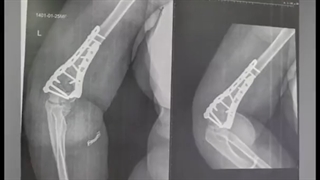

فیلم بدون سانسور جراحی شکستگی و در رفتگی آرنج